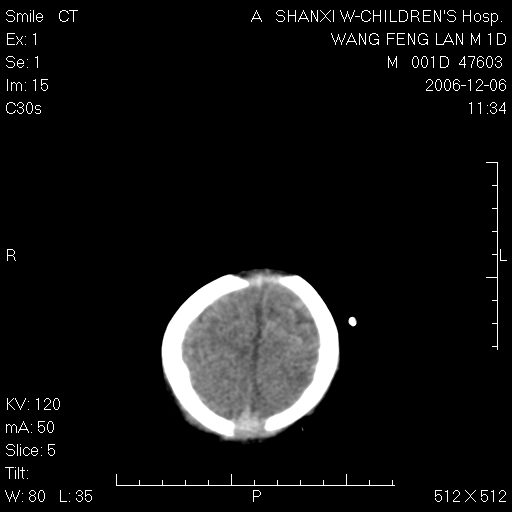

以下是引用zjzjr在2006-12-6 19:29:00的发言:[br]支持新生儿缺血缺氧性脑病伴少量蛛网膜下腔出血.

以下是引用卜一在2006-12-6 21:38:00的发言:[br][br] 支持:新生儿缺血缺氧性脑病伴少量蛛网膜下腔出血 [br]